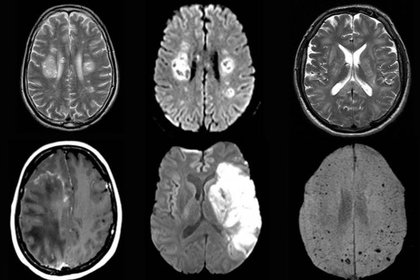

Cambios cerebrales en la resonancia magnética a tres meses en pacientes con COVID-19

Unos 60 pacientes recuperados y 39 controles fueron sometidos a resonancia magnética cerebral. La cohorte COVID-19 mostró una amplia gama de diferencias con respecto a los controles, incluidos volúmenes de materia gris bilaterales significativamente más altos en las cortezas olfativas y los hipocampos. Algunas de estas diferencias se asociaron con síntomas persistentes como pérdida de memoria y olfato. Los investigadores señalan que los hallazgos indican "el potencial de neuroinvasión del SARS-CoV-2 ... incluso si los pacientes se recuperan bien de la condición de neumonía, los cambios neurológicos pueden causar una gran carga". EClinicalMedicine, 3 de agosto de 2020